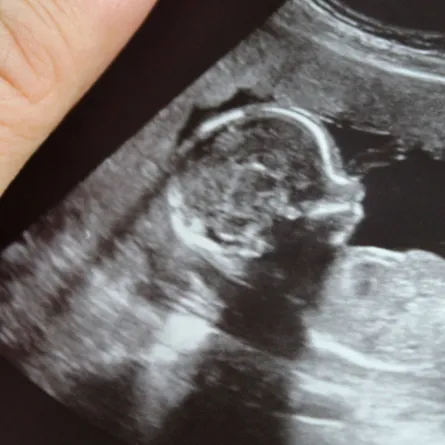

- بينت الدراسات أن بكتيريا أمعاء الحامل يختلف تأثيرها في الثلث الأول والثالث على الجنين أي في بداية الحمل والجنين.

- ترتبط هذه التغييرات بالحاجة إلى نقل الطاقة، والمواد الغذائية إلى الجنين الذي يتطور، وينمو ويكبر مع مرور شهور الحمل حتى الوصول إلى مرحلة الولادة.